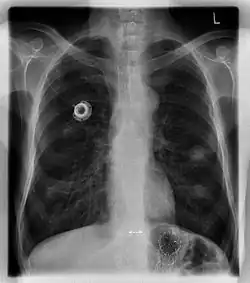

The port is usually inserted in the upper chest (known as a "chest port"), just below the clavicle or collar bone, with the catheter inserted into the jugular vein.

A port consists of a reservoir compartment (the portal) that has a silicone bubble for needle insertion (the septum), with an attached plastic tube (the catheter). The device is surgically inserted under the skin in the upper chest or in the arm and appears as a bump under the skin. It requires no special maintenance other than occasional flushing to keep clear. It is completely internal so swimming and bathing are not a problem. The catheter runs from the portal and is surgically inserted into a vein (usually the jugular vein or less optimally the subclavian vein). Ideally, the catheter terminates in the superior vena cava or the right atrium. This position allows infused agents to be spread throughout the body quickly and efficiently.

Ports can be put in the upper chest or arm. The exact positioning itself is variable as it can be inserted to avoid visibility when wearing low cut shirts, and to avoid excess contact due to a backpack or bra strap. The most common placement is on the upper right portion of the chest, with the catheter itself looping through the right jugular vein, and down towards the patient's heart.

A follow-up on a chest radiograph can immediately detect complications associated with the procedure such as pneumothorax, hemothorax and malpositions of the catheter. However, routine chest radiography is not needed due to the low complication rates associated with the procedure. The chest radiograph is only done if there is clinical suspicion of a complication.[4]